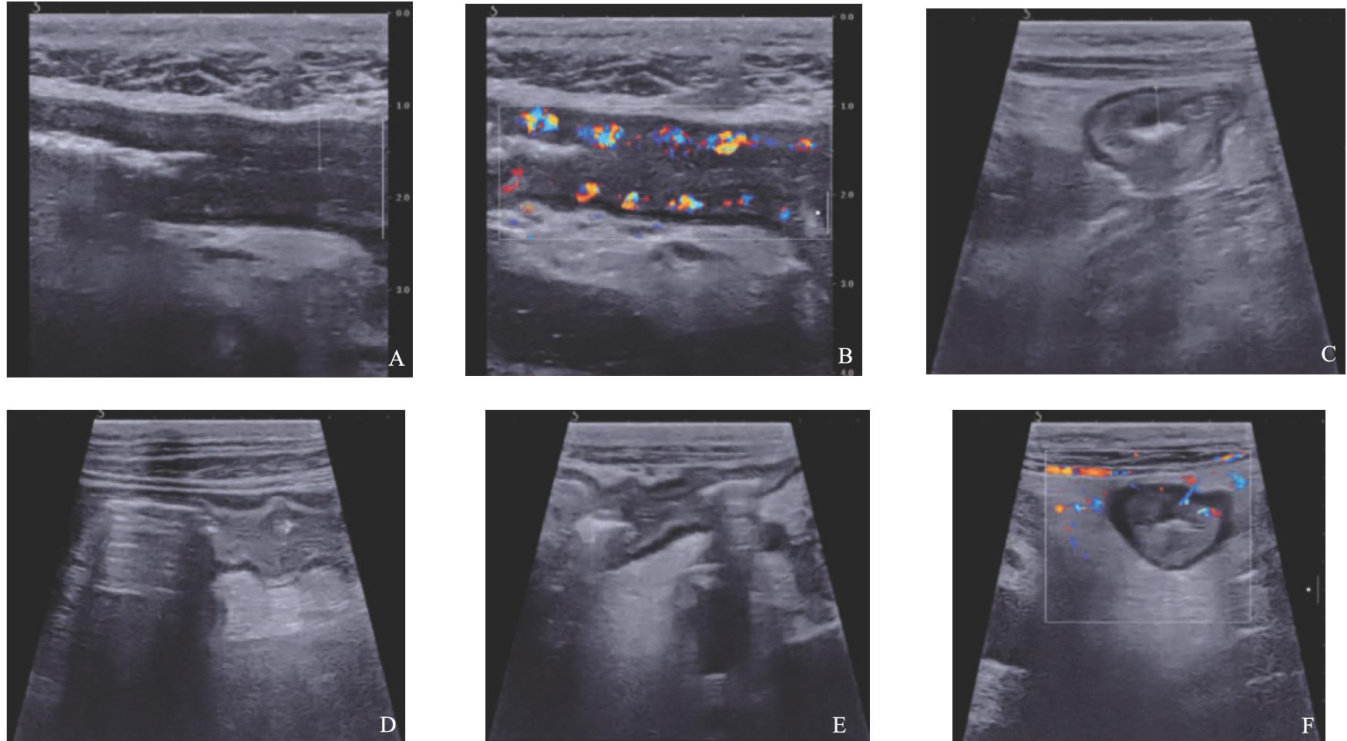

免疫检查点抑制剂相关性肠炎临床及超声表现一例

ABSTRACT:Immune checkpoint inhibitor-associated enterocolitis isan immune-related adverse reaction during tumor treatment with immune checkpoint inhibitors.In this article,we presentthe clinical data and ultrasound manifestations of apatient with immune checkpoint inhibitor-associated enterocolitis,aiming to share diagnosticand therapeutic insights.

免疫检查点抑制剂(immunecheckpoint inhibitors,ICI)可通过激活T细胞抗肿瘤免疫改善多种恶性肿瘤的预后,但其引发的免疫相关不良事件日益受到关注。(剩余7204字)